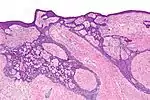

| Superficial basal-cell carcinoma (also known as "superficial multicentric basal-cell carcinoma") | Occurs most commonly on the trunk and appears as an erythematous patch.[19]: 748 [2] | ![]() | |

| Fibroepithelioma of Pinkus | Anastomosing epithelial strands in a fenestrated pattern[21] | Most commonly occurs on the lower back.[19]: 748 [2] | ![]() |